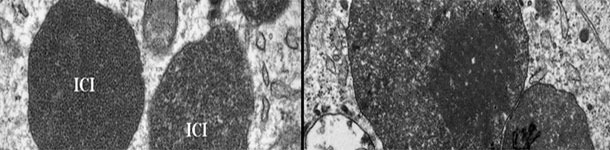

The PCV2 has been associated, in an ongoing way and throughout time, with more pathologies called, collectively, diseases associated with the PCV2 (PCVDs): PCV2 systemic disease, PCV2 lung disease, PCV2 enteric disease, PCV2 reproductive disease,PCV2 subclinical infection and porcine dermatitis and nephropaty syndrome.

Novelties about the excretion routes, the transmission routes, the risk factors, etc., and explanation about how the PCV2 becomes a pathogenic virus.